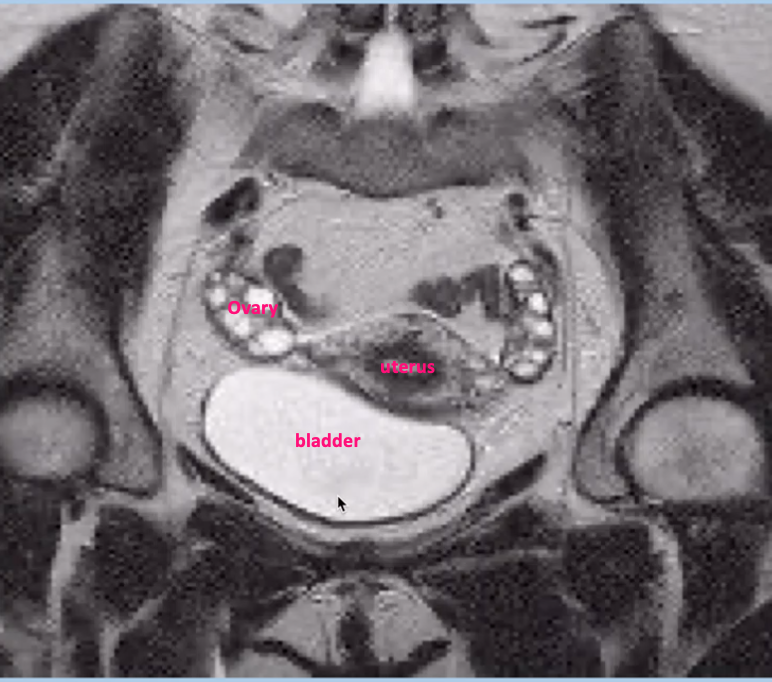

Imaging modality & complete the labels

Coronal MRI

Imaging modality and what is seen in the ovaries

T2 weighted MRI (fat & water are white)

Ovaries containing follicular cysts